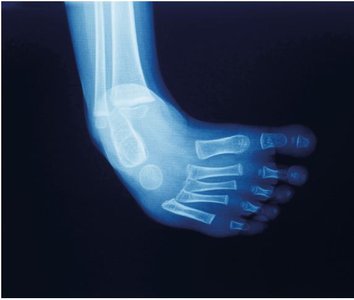

Leg, Ankle, and Foot

The femur joins the tibia to support body weight. The fibula is the smaller bone of the lower leg. The patella protects the knee joint. The tarsal bones in the ankle connect to the metatarsal bones in the foot, and each toe contains three phalanges (except the great toe, which has two).

Bones of the lower extremity including femur, tibia, fibula, patella, and foot bones Bones of the foot including tarsals, metatarsals, and phalanges

Hallux Valgus and Clubfoot

Hallux valgus is a deformity where the great toe is angled laterally, often resulting in a bunion. Clubfoot (talipes equinovarus) is a congenital deformity where the foot is pulled downward and inward.

Hallux valgus and bunion X-ray of clubfoot